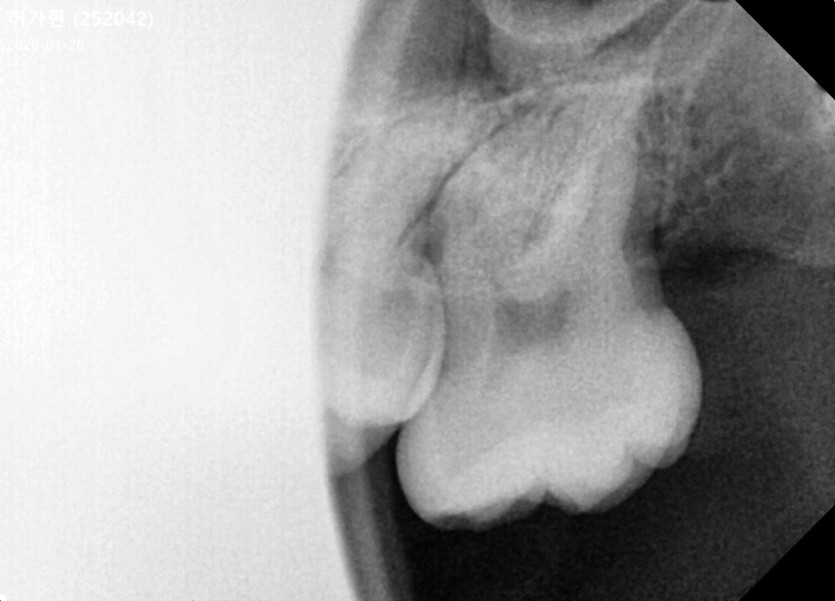

#28,38 사랑니 발치

구강외과 전문의가 당일 발치했습니다.